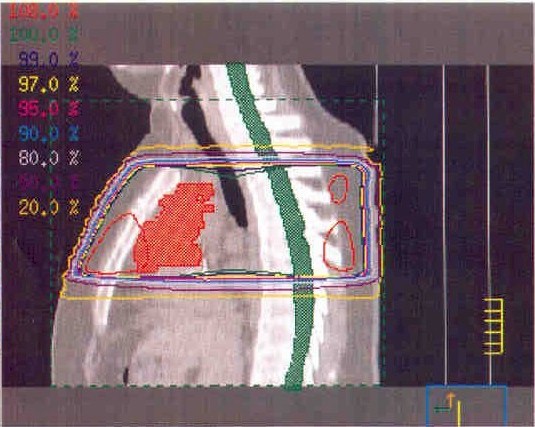

these are CT scan pictures and x-rays shoing the location of my tumor, it's current size, and the area that will be getting radiation therapy...

the bright red/orange solid area in the above pictures is my tumor.  the red outlined areas are where they are aiming the radiation through.